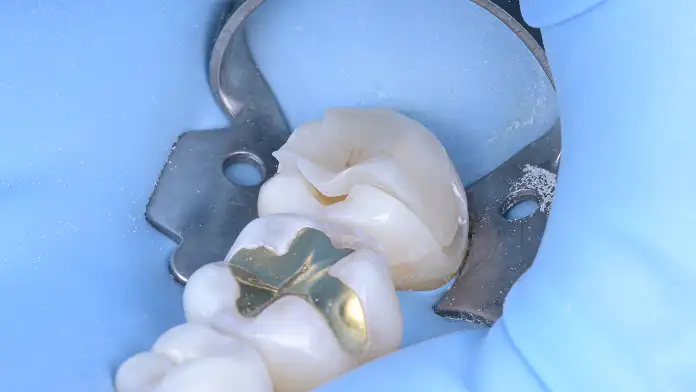

오차를 최소화하는 정밀한 보철 과정

정밀하게 제작된 보철물은 경계부에서의 오차를 최소화하고, 내면의 적합을 최대화하는 방향으로 제작됩니다.

안정적인 치료 결과를 위한 화학적인 내면 처리

보철물이 치아와 하나로 결합하기 위해서는 보이지 않는 표면의 상태가 중요합니다. 세라믹 내면의 산 부식 처리(etching)와 실란(silane)의 처리 등 과학적인 표면 처리를 통해, 탈락과 파절을 방지하는 강력한 화학적 결합을 이끌어냅니다.